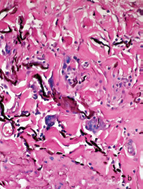

The possibility of TL, BTL, or type 1 leprosy reaction R1, was strongly suspected. PAS, Ziehl-Neelsen (ZN) and Grocott stains didn’t show germs. Small and medium sized vessels were surrounded by giant cells and lymphocytes and elastic fibers stain showed their absence or diminution in the lesion or in the vessels or their phagocytosis by the giant cells (Figure 6).

Figure 6a Medium size vein surrounded by abundant giant cells and lymphocytes.

Figure 6b Elastic stain demonstrates giant cells phagocytosing elastic fibers. A: HE, 20X. B, 40 X.